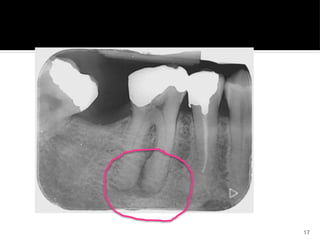

Radiographic features

 Thickening and apparent blunting of

root with rounding of apex

 Apex appears bulbous

 Lamina dura will follow the outline of

teeth in normal periodontal ligament

space

 Irregular accumulation of cementum

that is accommodated by related area

of bone resorption

17